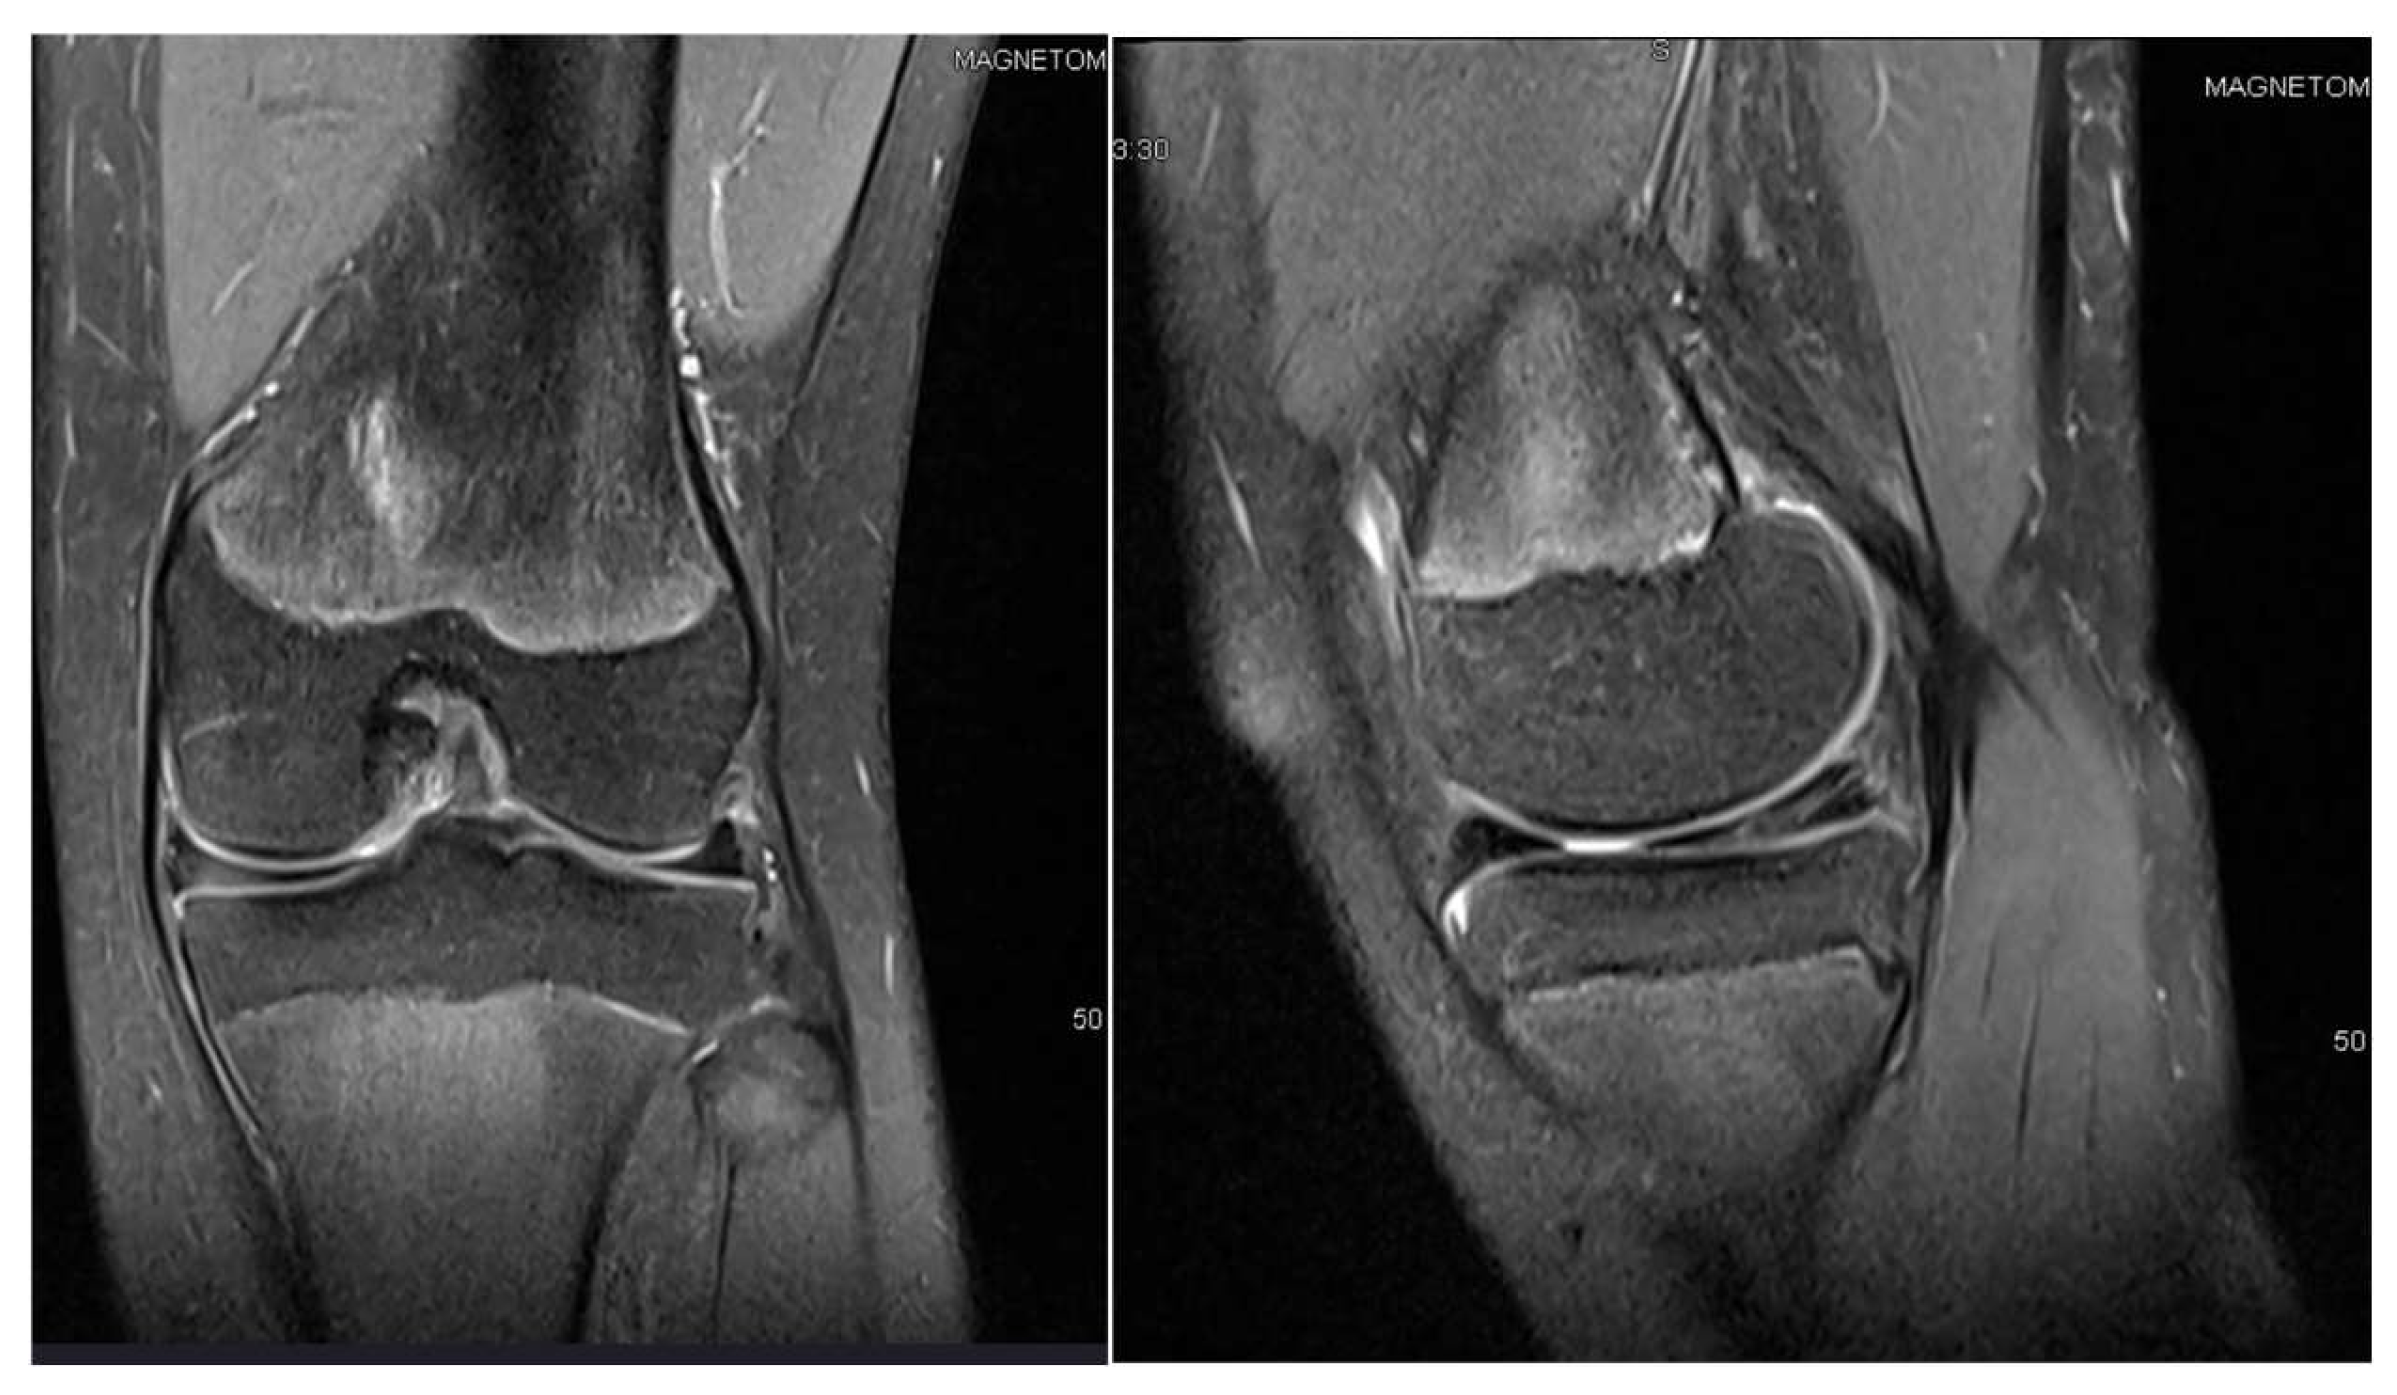

3.3. Case 3—G.L.

| G.L. | 14 | Bilateral (symptomatic right) | Pain, medial tenderness, normal ROM | Basketball | 1 surgery: partial meniscectomy and suture for horizontal tear (14) | 6 months: symptom-free, full ROM |